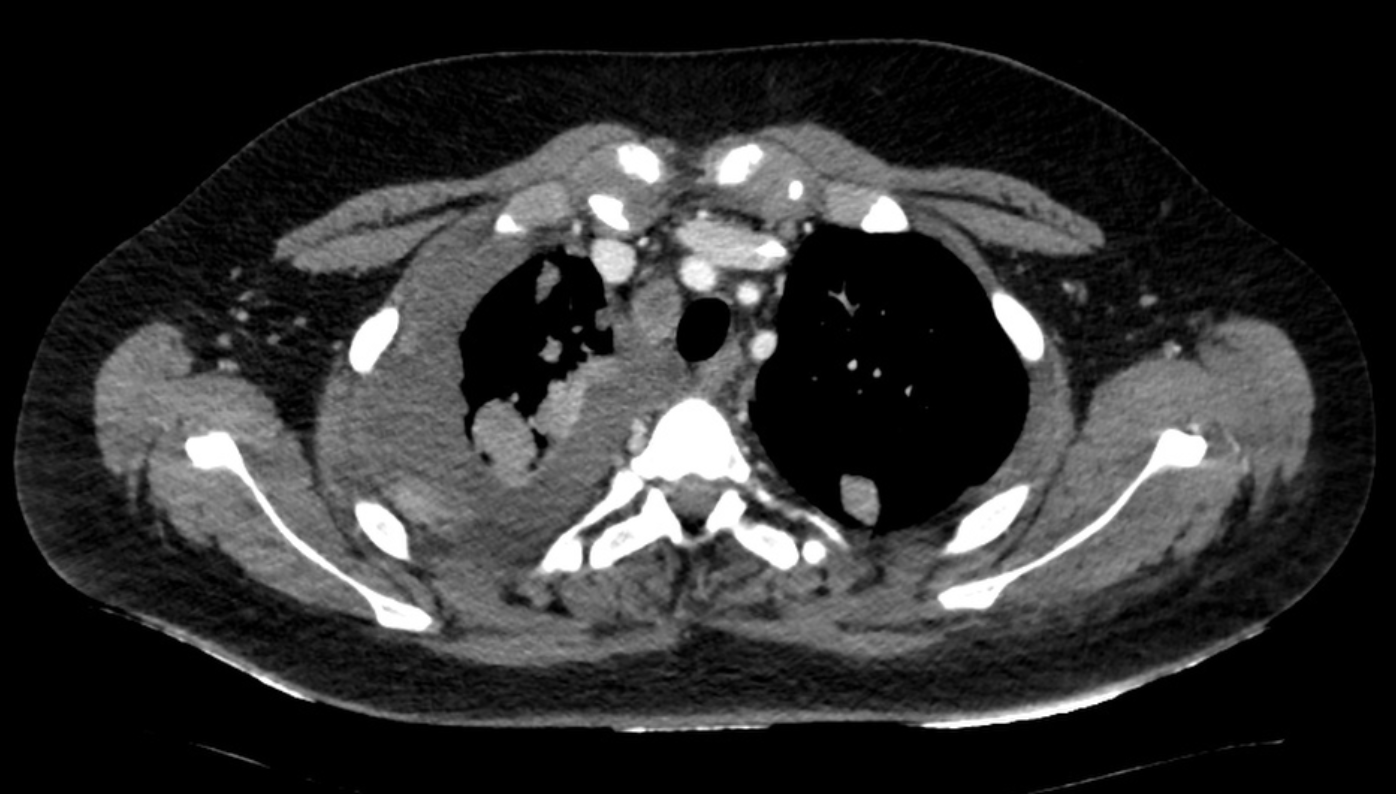

Initial chest CT findings: Massive right sided pleural effusion can be seen, along with multiple metastatic nodules affecting the lung parenchyma and parietal pleura

Figure 1. Initial chest CT findings: Massive right sided pleural effusion can be seen, along with multiple metastatic nodules affecting the lung parenchyma and parietal pleura

A 14-year-old male with a history of Ewing sarcoma, initially treated with chemotherapy and local control, presented with progressive shortness of breath. Initial lung ultrasound demonstrated a 4.5-cm homogeneous pleural effusion in the right hemithorax, without evidence of loculations. A diagnostic and therapeutic thoracentesis was performed, yielding 500 mL of serosanguinous fluid. Cytology was consistent with malignant effusion. Four days later, repeat ultrasound and chest CT demonstrated recurrence (Figure 1.).